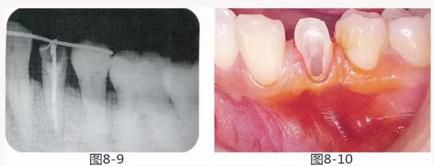

圖8-9 同時期的X光照片。牙槽骨無變化。

圖8-10 約一個月后,進行牙周外科治療之前的狀態(tài)。附著齦較少。